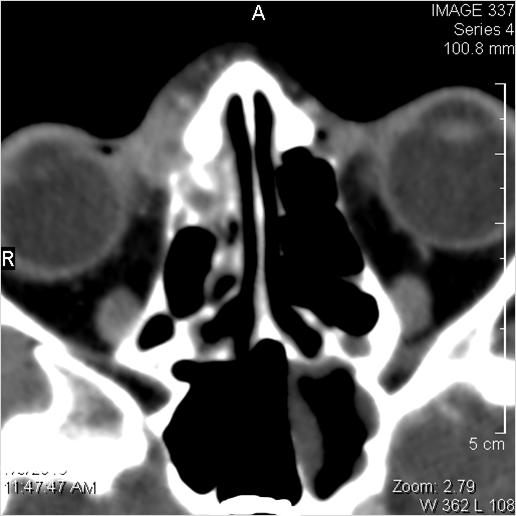

Nasal Cavity and Nasolacrimal Drainage System

There is mucoperiosteal thickening in the nasal cavity.

There is mucosal thickening of the posterior lateral walls of the nasal cavity, cribriform plate or the face of the sphenoid bone.

There is infiltration of soft tissues or bone erosion along the nasolacrimal fossa or canal.

Sinuses

There is mucoperiosteal thickening in the sinuses.

There is mucosal enhancement in the sinuses.

There is bone erosion along the walls of any affected sinuses.